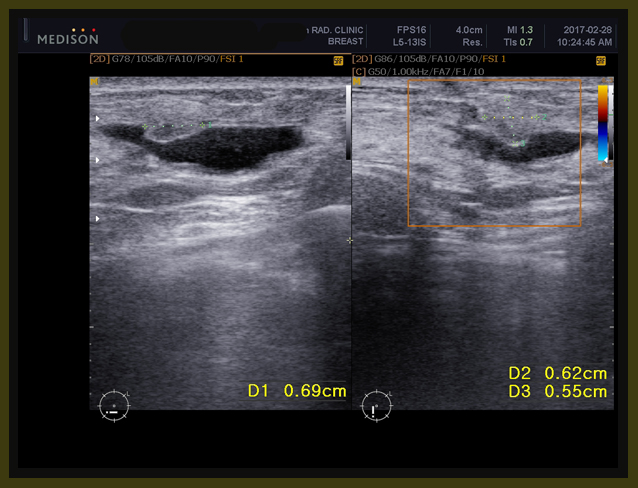

양측에 침윤성 유방암으로 수술을 하게 되었고(2017/12/26) 병기는 1기였다. 이후에 2017년 1월 말부터 방사선 치료를 양측 수술 부위에 시행하였다. 당시의 자료를 보면 다음과 같다.

0-3

수술 전의 초음파 자료에 양측에 각기 1.92×0.7cm(right breast 12시 방향 5cm 거리)와 0.69×0.51cm(left breast 7시 방향 4cm 거리)의 두개의 크지 않은 종양이 보였다.

I000012I000013

이후에 이 환자를 본원의 한방 항암약물로서 소양인에게 적합한 R0052와 위에서 설명했듯이 양방의 소양인 치료법인 femara+ arimidex 요법과 더불어서 철저한 식이요법을 시행시켰고, 약 12일 뒤인 2월 28일 다시 초음파 체크를 하였다. 이같이 빠른 체크를 2주 내에 하는 이유는 약물의 방향이 맞는가 약물의 농도가 맞는가를 알기 위해서이다. 그 결과는 다음과 같다.

1-8

2주간의 한양방 결합요법의 결과 3항에서 보듯이 약 7mm 정도의 전에 잔류 종양으로 보이던 부분이 약간 줄어들었고, 자궁주위에 있던 난소의 종양은 6.8×5.9x 8.1cm의 크기가 5.5×4.7×6.7cm 로 체적대비해서 171 cc가 91 cc로 100%의 종양이 53%로 절반 가량이 줄어들었고, 자궁내벽의 비후는 여전히 보이고, 3cm 크기의 근종으로 보이는 종양은 차이가 없었다.